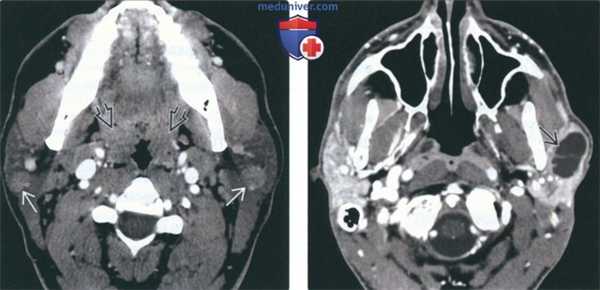

(Справа) КТ с КУ, аксиальная проекция. У ВИЧ-пациента в обеих околоушных железах (их плотность повышена) определяются множественные микрокисты. Такая картина характерна для доброкачественного лимфоэпителиальною поражения. Обратите внимание на гипертрофию глоточной миндалины. (Слева) КТ с КУ, аксиальная проекция. Крупные многокамерные кисты в обеих околоушных железах у пациента с ВИЧ. Внутри кисты видны перегородки.

(Справа) КТ с КУ, аксиальная проекция. Двусторонние кистозные образования околоушных желез с узловатым строением стенок (лимфоидные фолликулы) у пациента с ВИЧ. При доброкачественном лимфоэпителиальном поражении в железах могут возникать как кисты, так и солидные объемные образования. Обратите внимание на гипертрофию небных миндалин.

(Слева) КТ с КУ, аксиальная проекция. В обеих околоушных железах визуализируются солидные образования с четкими контурами. И хотя метастазы и лимфома могут выглядеть точно так же, гипертрофия небных миндалин позволяет заподозрить лимфоэпителиальное поражение или хроническую лимфаденопатию околоушных лимфоузлов при ВИЧ.

(Справа) КТ с КУ, единичная киста в левой околоушной железе, разделенная внутренней перегородкой. И хотя при доброкачественном лимфоэпителиальном поражении обычно обнаруживается сразу несколько образований, иногда они могут быть и единичными. В такой ситуации может быть выставлен неверный диагноз - киста первой жаберной щели.

(Слева) На аксиальной КТ с КУ визуализируются хорошо отграниченные солидные контрастиру-ющиеся очаги в обеих околоушных железах. Метастазы и лимфома могут выглядеть аналогично, но гипертрофия миндалин позволяет предположить ДЛЭП или персистирующую лимфаде-нопатию околоушных желез, обусловленную ВИЧ.

(Справа) На аксиальной КТ с КУ в левой околоушной железе визуализируется солитарное образование, разделенное перегородками. ДЛЭП обычно являются множественными, но возможны и солитарные поражения.

(Слева) На аксиальной КТ с КУ визуализируются множественные мелкие контрастирующиеся очаги с диффузным поражением обеих околоушных желез, характерные для персистирующей генерализованной паротидной лимфаденопатии. Данные очаги представляют собой увеличенные лимфоузлы.

(Справа) На корональной реформатированной КТ с КУ у пациента с ВИЧ определяются очаги в обеих околоушных железах, образованные кистозным и солидным компонентами, сопоставимые с ДЛЭП при ВИЧ.